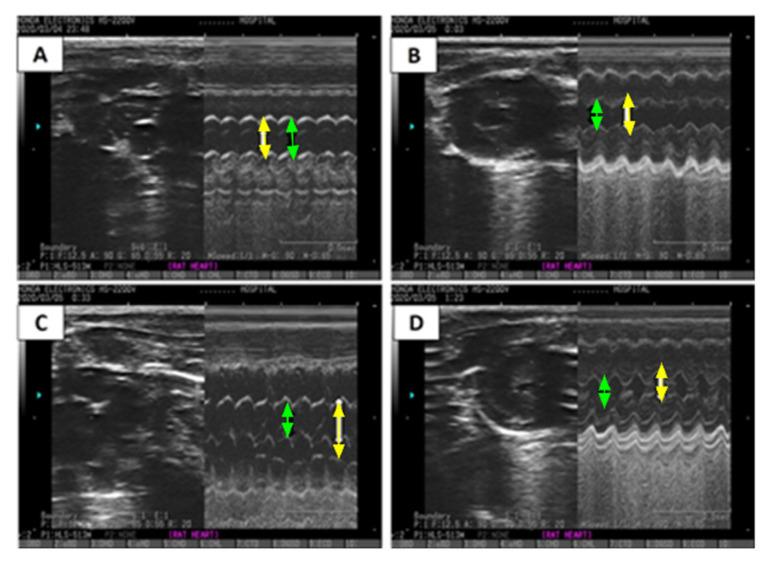

Irreversible myocardial injury causes the exhaustion of cellular adenosine triphosphate (ATP) contributing to heart failure (HF). Cyclocreatine phosphate (CCrP) was shown to preserve myocardial ATP during ischemia and maintain cardiac function in various animal models of ischemia/reperfusion. We tested whether CCrP administered prophylactically/therapeutically prevents HF secondary to ischemic injury in an isoproterenol (ISO) rat model. Thirty-nine rats were allocated into five groups: control/saline, control/CCrP, ISO/saline (85 and 170 mg/kg/day s.c. for 2 consecutive days), and ISO/CCrP (0.8 g/kg/day i.p.) either administrated 24 h or 1 h before ISO administration (prophylactic regimen) or 1 h after the last ISO injection (therapeutic regimen) and then daily for 2 weeks. CCrP protected against ISO-induced CK-MB elevation and ECG/ST changes when administered prophylactically or therapeutically. CCrP administered prophylactically decreased heart weight, hs-TnI, TNF-α, TGF-β, and caspase-3, as well as increased EF%, eNOS, and connexin-43, and maintained physical activity. Histology indicated a marked decrease in cardiac remodeling (fibrin and collagen deposition) in the ISO/CCrP rats. Similarly, therapeutically administered CCrP showed normal EF% and physical activity, as well as normal serum levels of hs-TnI and BNP. In conclusion, the bioenergetic/anti-inflammatory CCrP is a promising safe drug against myocardial ischemic sequelae, including HF, promoting its clinical application to salvage poorly functioning hearts.

不可逆性心肌损伤会导致细胞三磷酸腺苷(ATP)耗竭,进而引发心力衰竭(HF)。环磷酸肌酸(CCrP)已被证明在多种缺血/再灌注动物模型中,于缺血期间可保存心肌ATP并维持心脏功能。我们测试了在异丙肾上腺素(ISO)大鼠模型中,预防性/治疗性给予CCrP是否能预防缺血性损伤继发的HF。39只大鼠被分为五组:对照组/生理盐水组、对照组/CCrP组、ISO/生理盐水组(连续2天皮下注射85和170 mg/kg/天),以及ISO/CCrP组(腹腔注射0.8 g/kg/天),ISO/CCrP组在ISO给药前24小时或1小时(预防性方案)或在最后一次ISO注射后1小时(治疗性方案)给药,然后每天给药2周。预防性或治疗性给予CCrP可预防ISO诱导的肌酸激酶同工酶(CK-MB)升高及心电图/ST段改变。预防性给予CCrP可降低心脏重量、高敏肌钙蛋白I(hs-TnI)、肿瘤坏死因子-α(TNF-α)、转化生长因子-β(TGF-β)和半胱天冬酶-3,同时增加射血分数(EF%)、内皮型一氧化氮合酶(eNOS)和连接蛋白43,并维持身体活动能力。组织学检查表明,ISO/CCrP组大鼠的心脏重塑(纤维蛋白和胶原蛋白沉积)明显减少。同样,治疗性给予CCrP可使EF%和身体活动能力正常,hs-TnI和脑钠肽(BNP)的血清水平也正常。总之,具有生物能量/抗炎作用的CCrP是一种有前景的安全药物,可对抗包括HF在内的心肌缺血后遗症,促进其在挽救功能不良心脏方面的临床应用。